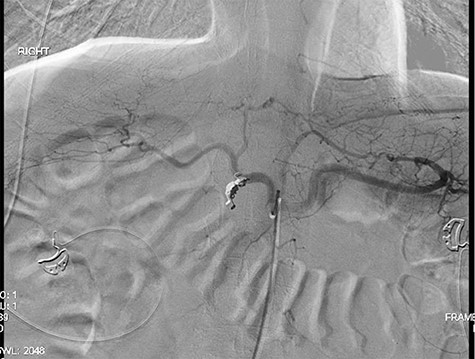

Three years later, the patient presented to the emergency department with epigastric pain as well as melena. The patient could not remember the last time he took any acid suppression medication. He had increased his intake of ibuprofen. The patient was found to have a Hgb of 6.5 g/dl. He was given 2 U of PRBC and was taken to the endoscopy suite by the gastroenterology team. The endoscopy demonstrated a posterior duodenal bulb ulcer with a metallic ring in the center (Fig. 3). At this point, the general surgery team was consulted. A computed tomography scan of his abdomen and pelvis was obtained to further guide our operative decision-making (Fig. 4).

A laparoscopic distal gastrectomy and partial duodenectomy with antecolic antegastric Roux-en-Y reconstruction with a pancreaticobiliary limb of 50 cm and the Roux limb of 50 cm and esophagogastroduodenoscopy were performed. As the patient had been positive for Helicobacter pylori on endoscopic biopsy and there was increased concern for his use of alcohol as well as his living situation, a definitive acid suppression operation was also performed. The pathology returned as chronic gastritis with associated ulcer with mild metaplasia, the H. pylori on immunohistochemistry was positive. The patient on postoperative day (POD) 1 had a swallow study, which demonstrated a patent gastrojejunostomy with adequate flow distally (Fig. 5). On POD 5 the patient was discharged on a proton pump inhibitor and treatment for his H. pylori.